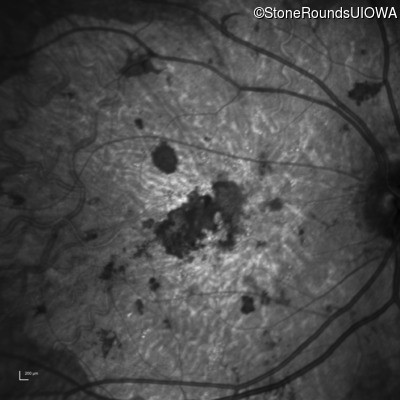

Infrared Fundus Photograph - Right - 20/150 sc

Exemplar